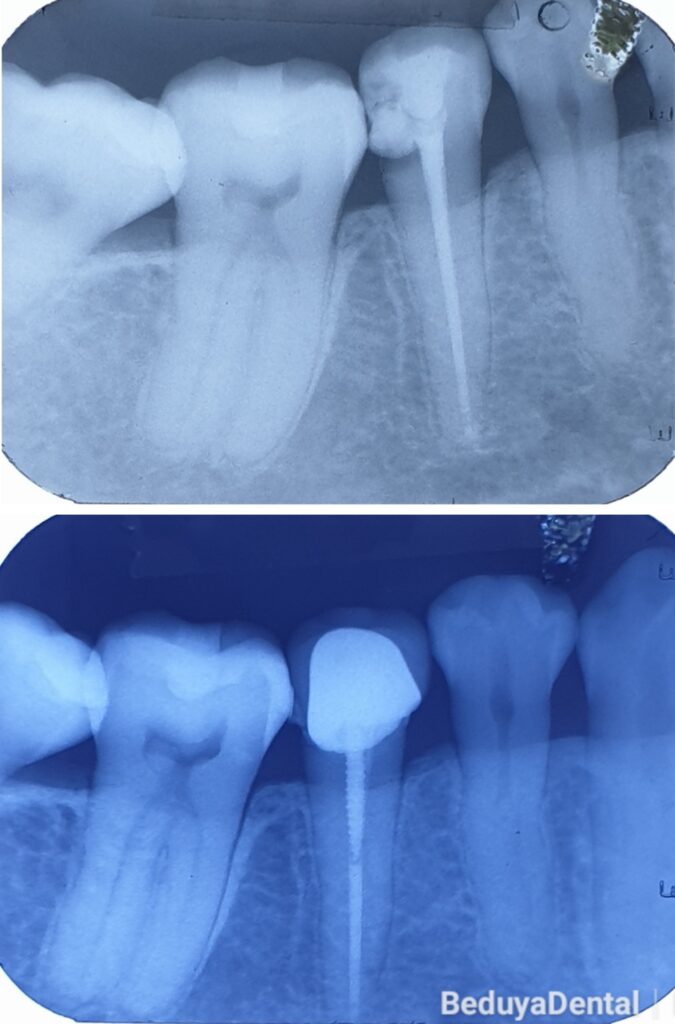

Post and Crown Before & After Photos in Manila

At Beduya Dental in Manila, we use post and crown restorations to rebuild teeth that have been severely damaged or structurally compromised — often following root canal treatment. A dental post is carefully placed into the root canal to create a stable foundation, allowing a crown to be securely attached and fully restore the tooth’s strength and appearance. Our before and after photos showcase real patients who came to us with heavily damaged teeth and left with a strong, natural-looking, long-lasting result. Browse our patient gallery below and see why patients across Manila trust Beduya Dental for post and crown and complete tooth restoration needs.